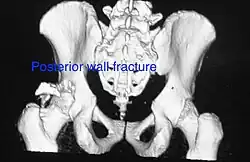

Posterior wall This is the most common variety of acetabular fracture. It typically occurs due to dashboard injury; when a person travelling in a vehicle involved in a head-on collision, the force applied over the flexed knee travels along the femur bone to the head of the femur, breaking the posterior wall of the acetabulum. The head of the femur is dislocated outside the joint. T shape When a transverse fracture also had a vertical fracture line, it is called a T shape fracture. Here the innominate bone is broken in such a way that all three parts of it, the ilium, the ischium and the pubis are separated from one another. This is a three part fracture. Though both columns are broken, the weight bearing dome is still attached to the main part of the ilium and hence it is not a true fracture of both columns.

Posterior column As with posterior wall injury, this also typically occurs due to dash board injury. Posterior column + Posterior wall These fractures are extensions of elementary fractures. With the involvement of the posterior wall, the difficulty in treatment increases. These fractures are rarely amenable to non-surgical treatment. Due to posterior wall fracture, the hip is usually dislocated posteriorly, requiring immediate reduction of dislocation and surgical reconstruction after a few days.